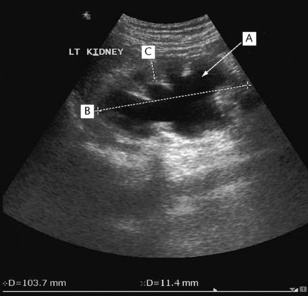

Ultrasonography is a non-invasive technique that involves high-frequency sound waves. It can accurately assess the size, shape and position of the kidney, and can also distinguish solid masses and renal cysts (Figs 8.17 and 8.18). Dilatation of the pelvicalyceal system and upper ureters can also be detected – suggesting the presence of urinary tract obstruction. This is a major cause of reversible renal failure, and can be treated if detected early enough. Transrectal ultrasound (TRUS) can also assess prostate size and be used to guide a prostate biopsy (Fig. 8.19). Renal vein thrombosis can be detected with Doppler ultrasonography, and arterial Doppler studies can be used to identify renal artery stenosis. The specificity and sensitivity of ultrasound investigations are very operator-dependent.

image

Fig. 8.18 Hydronephrosis of the left kidney demonstrated by ultrasonography. The echolucent (black) areas within the kidney are caused by dilated calyces (A). The bipolar length (B) of the kidney is normal and the cortical thickness (C) is well preserved, suggesting that prompt relief of the obstruction will allow good functional recovery.